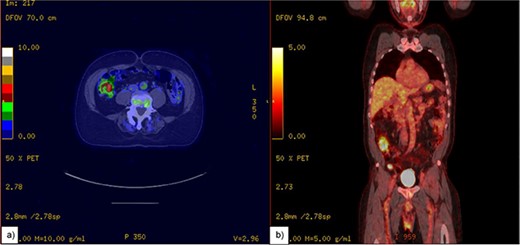

MCL often starts with lymph node enlargement and can spread to the bone marrow, liver, and gastrointestinal tract, especially the colon. It rarely affects the appendix, typically through nearby ileocecal involvement [4, 5]. In our case, a 1.4 cm appendiceal mass was found on a positron emission tomography CT (PET-CT) scan a year prior to presenting with the symptoms, but follow-up was not pursued until the patient presented with pain and obstructive symptoms due to an enlarged appendix, confirmed by CT to be a “swirl sign” indicative of volvulus (Figs 1 and 2). The appendix measured 5 cm in width and 16.5 cm in length (Figs 3–5).

A PET-CT scan of appendix. (a) Thickening of the appendix measuring up to 1.4 cm with increased Fluorodeoxyglucose (FDG) avidity. (b) Showing appendix in coronal view.